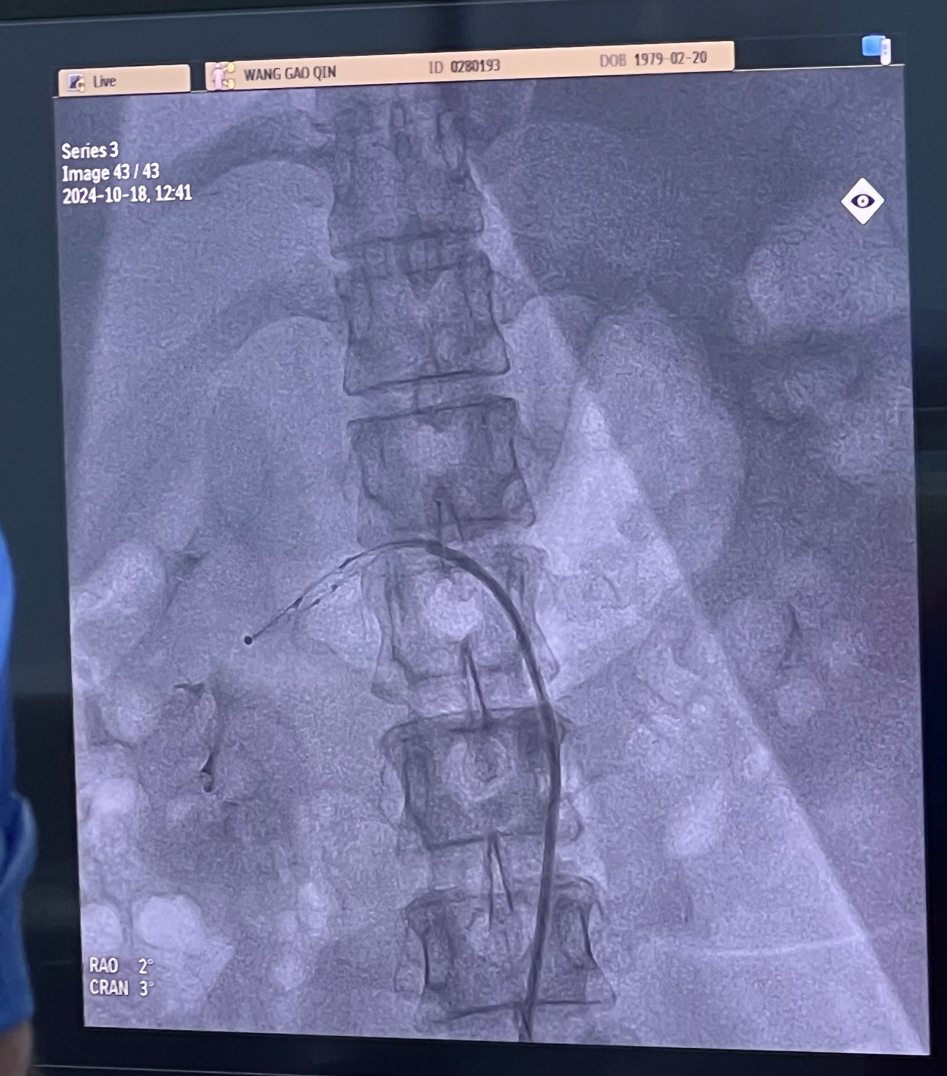

患上高血压后,药物治疗效果不佳或依从性差,导致血压忽高忽低,应该怎么办?45岁的王女士就是一名深受难治性高血压困扰的患者。庆幸的是,云南省阜外心血管病医院通过微创技术——经皮去肾神经术(以下简称“RDN手术”),为她稳定了血压。

10月22日,健康君从云南省阜外医院获悉,采用Netrod系统(网状多电极肾动脉射频消融系统)的RDN治疗技术不仅是西南地区首例,也标志着高血压治疗从“单纯药物治疗”迈向了“微创介入治疗”的新时代,为难治性高血压患者的治疗打开了新路径。